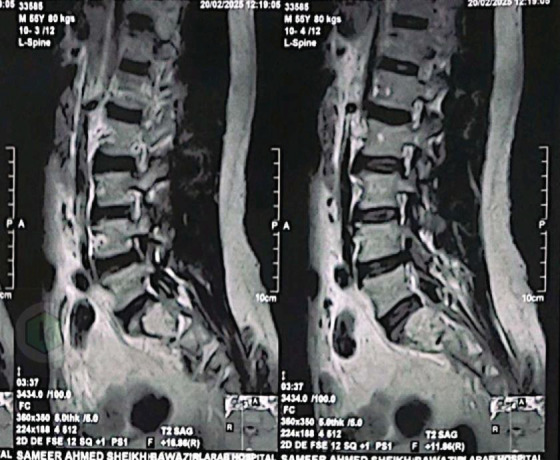

This case report describes a rare occurrence of a single isolated sacral metastasis in a 59-year-old male with clear cell renal cell carcinoma (ccRCC). The patient presented with progressive lower back pain and sacral numbness following a fall. Initial imaging revealed a destructive lytic lesion in the S1-S2 region and a left renal mass. A CT-guided biopsy of the sacral lesion confirmed metastatic ccRCC. PET-CT confirmed no additional metastases. Multidisciplinary management included partial left nephrectomy for the primary renal tumor, stereotactic body radiotherapy (SBRT; 45 Gy/15 fractions) targeting the sacral metastasis, and immunotherapy with sunitinib. The patient experienced significant pain relief within 1-week post radiotherapy and demonstrated stable disease with near-resolution of the sacral lesion at 3-month follow-up. At 12 months, imaging confirmed sustained disease stability. This case highlights the importance of considering metastatic RCC in patients with isolated sacral lesions, even in the absence of disseminated disease, and underscores the efficacy of combining localized ablation, radiotherapy, and targeted systemic therapy. Early diagnosis and a tailored multidisciplinary approach are critical for optimizing outcomes in such rare presentations.

本病例报告描述了一例59岁男性透明细胞肾细胞癌(ccRCC)罕见的单一孤立的骶骨转移。患者在跌倒后出现进行性腰痛和骶部麻木。初步影像学显示S1-S2区破坏性溶解性病变和左肾肿块。ct引导下的骶骨病变活检证实转移性ccRCC。PET-CT证实无其他转移。多学科治疗包括原发性肾肿瘤的左肾部分切除术,针对骶骨转移的立体定向放射治疗(SBRT; 45 Gy/15分数)和舒尼替尼免疫治疗。患者放疗后1周内疼痛明显缓解,3个月随访时病情稳定,骶骨病变接近消退。12个月时,影像学证实疾病持续稳定。该病例强调了在孤立性骶骨病变患者中考虑转移性RCC的重要性,即使在没有弥散性疾病的情况下,也强调了局部消融、放疗和靶向全身治疗联合治疗的有效性。早期诊断和量身定制的多学科方法对于优化此类罕见表现的结果至关重要。